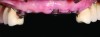

Fig 4. Before final impression making, the ovate pontic receptor sites and emergence profiles can be seen. They are created with the aid of the provisional prosthesis.

4

Figure 4